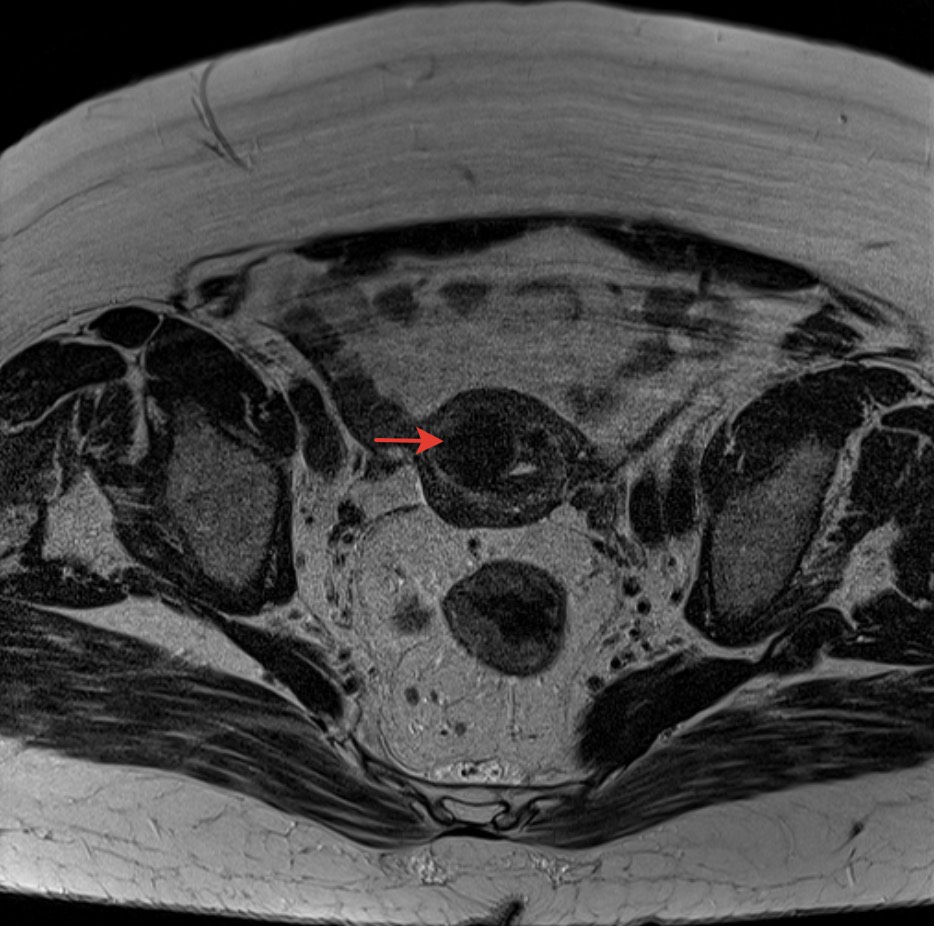

2895. Указанное стрелкой на представленных мр-томограммах образование соответствует